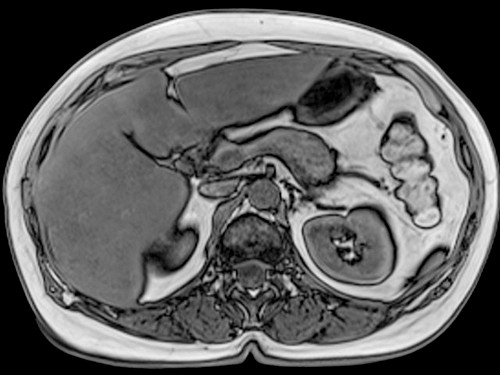

Заболевания пищеварительной системы сложно выявить на начальной стадии, с чем связана высокая частота запущенных раков желудочно-кишечного тракта. Нативное МРТ желудка и поджелудочной железы определяет воспалительные изменения, органическую патологию (раки), врожденные и приобретенные аномалии, сосудистую патологию.

Из всех органов брюшной полости поджелудочная железа относится к одним из самых сложных в обследовании: ее заболевания затруднительно диагностировать. Зачастую симптомы на начальных стадиях оказываются слабовыраженными и ярче проявляются лишь при активном развитии патологического процесса. МРТ-обследование является единственным, позволяющим выявить болезнь на ранних стадиях, что поможет предотвратить развитие. По этой причине при подозрениях на заболевания поджелудочной имеет смысл незамедлительно пройти МР-томографию.

МР-томография дифференцирует опухоли, выявляет кровотечения, диагностирует камни в протоках, является средством динамического контроля хода постоперационного периода после резекции опухоли.

Если делать МРТ поджелудочной железы в Москве и СПб, для выявления описанных нозологий врачи-радиологи предлагают комбинированный алгоритм с использованием взвешенного сканирования, динамического контрастного усиления, холангиопанкреатографии.

МРТ поджелудочной железы: что показывает

Нозологические формы, поражающие верхние отделы желудочно-кишечного тракта, многообразны. Смертельную опасность представляют опухоли (инсулинома, гастринома, глюкагонома, ППома, ВИПома, соматостатинома). С помощью мрт печени и поджелудочной железы (холангиопанкреатография) удается выявить раки диаметром более 1 мм. Для верификации метастазов в отдаленные и близлежащие лимфоузлы, оценки размеров патологического очага назначается динамическое усиление (МР-ангиография).